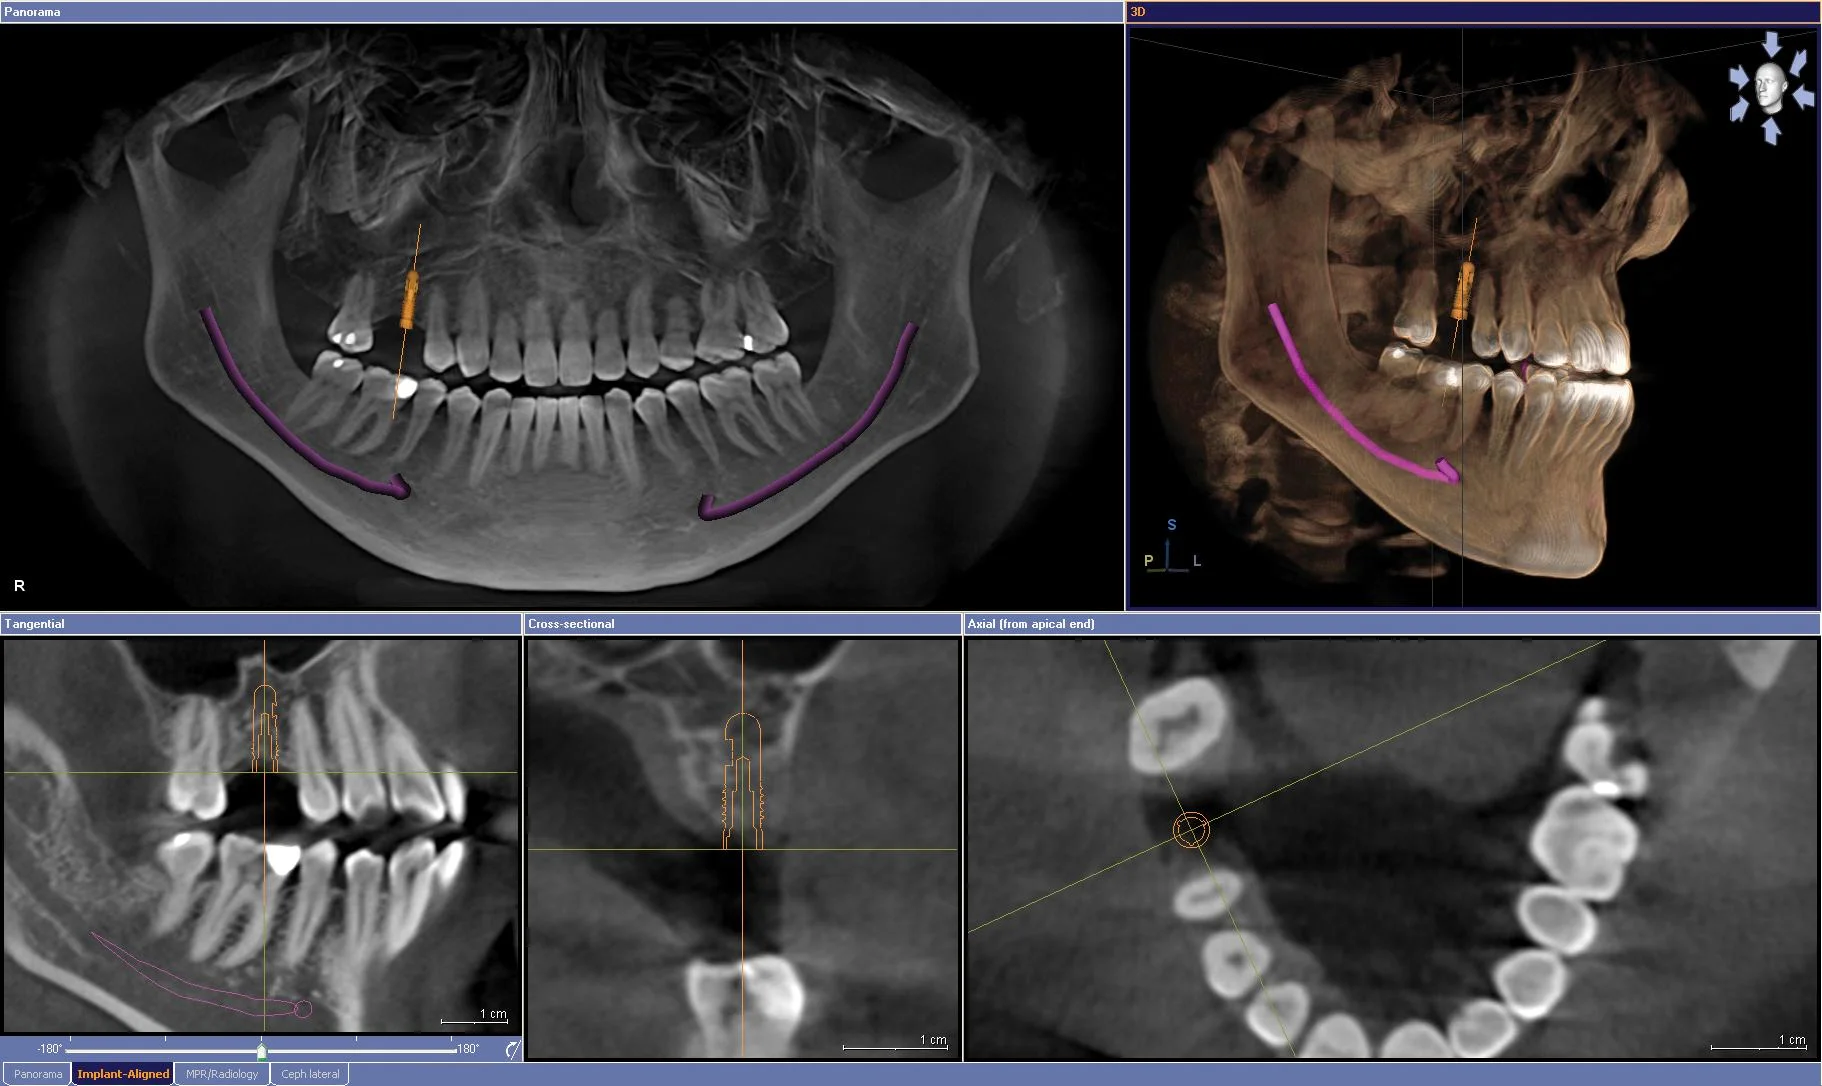

/Op 12 januari 2017 is de Nederlandse wetenschappelijke vereniging voor DentoMaxilloFaciale Radiologie (afgekort NVDMFR) opgericht. De vereniging stelt zich tot doel wetenschappelijke en praktische kennis omtrent tandheelkundige en maxillofaciale radiologie, beeldvorming, diagnostiek en stralenbescherming te bevorderen, te verbreiden en in het tandheelkundig werkveld te integreren.